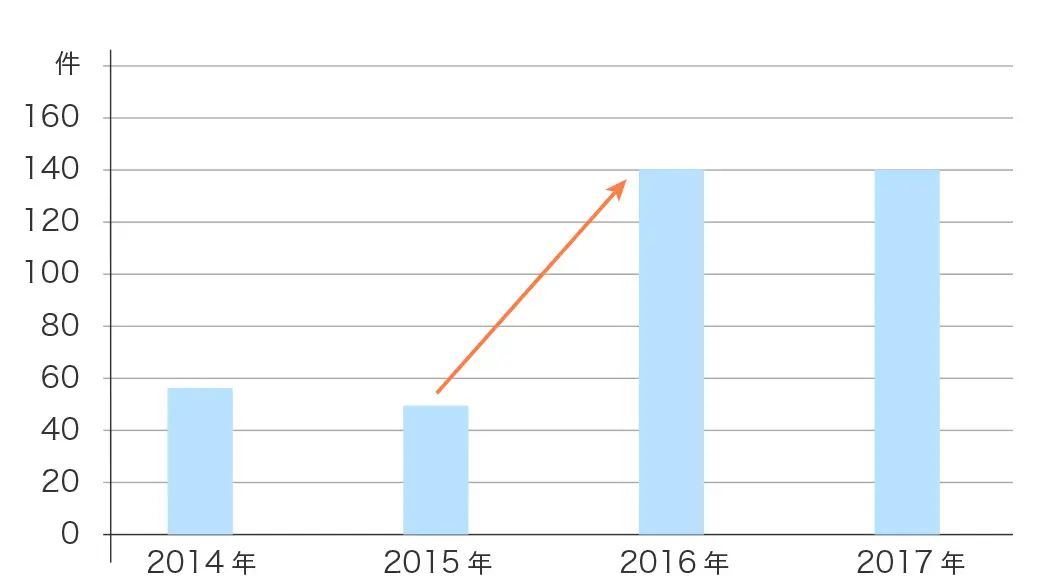

湘南藤沢徳洲会病院のESD件数

ほとんどの患者様が5日で退院されており、外科手術より早く退院出来ます(ESDは、1週間程度の入院とする病院が多いです)。